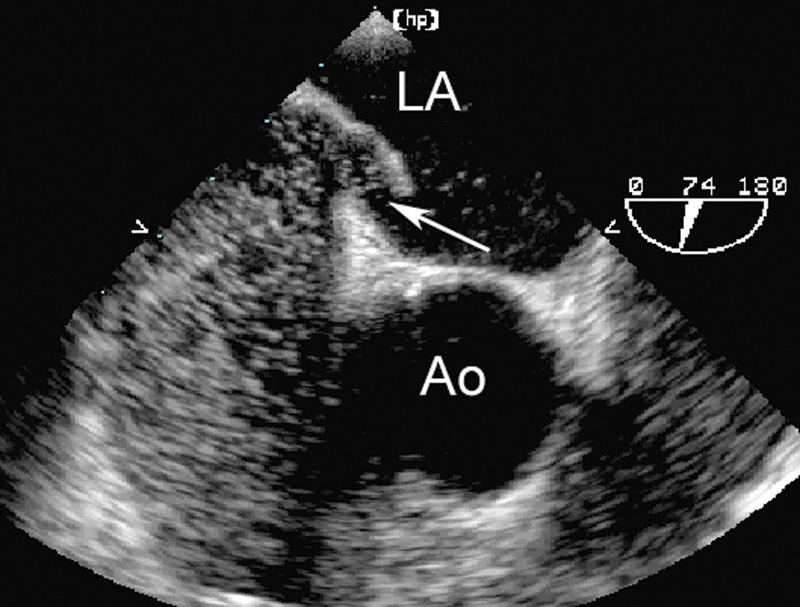

فحوصات تشخيصية لبعض امراض القلب والشرايين التاجية